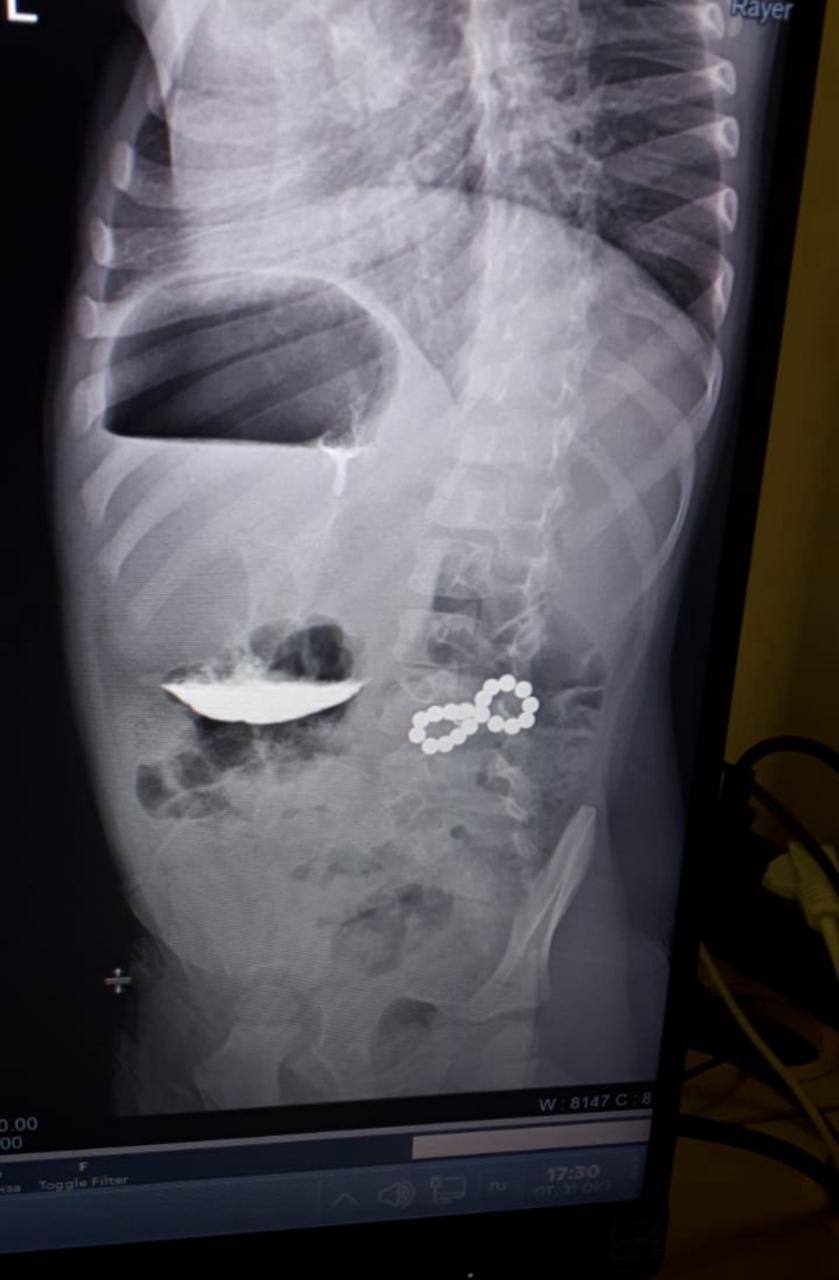

Ребёнок стал жаловаться на кашель. Во время планового рентген-обследования лёгких у ребёнка нашли несколько инородных тел. Магниты, оказавшись в разных петлях кишечника, с огромной силой притягивались друг к другу, сдавливая его стенки. Это могло привести к некрозу, перитониту и тяжелейшим последствиям для жизни.

Малыша срочно прооперировали. 18 магнитов извлекли из двенадцатиперстной и толстой кишки.